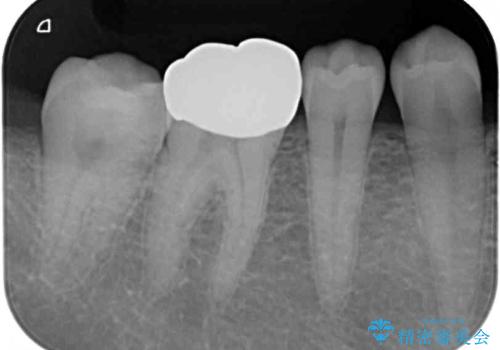

- 口を開けたときに目立ってしまう銀歯をセラミックに替えたいとのことで来院された患者様です。

以前むし歯治療を受けたときは時間がなかったため、近医で銀歯を入れたようですが、周囲の目線が気になるとのことでフルジルコニアクラウンにて補綴することとしました。